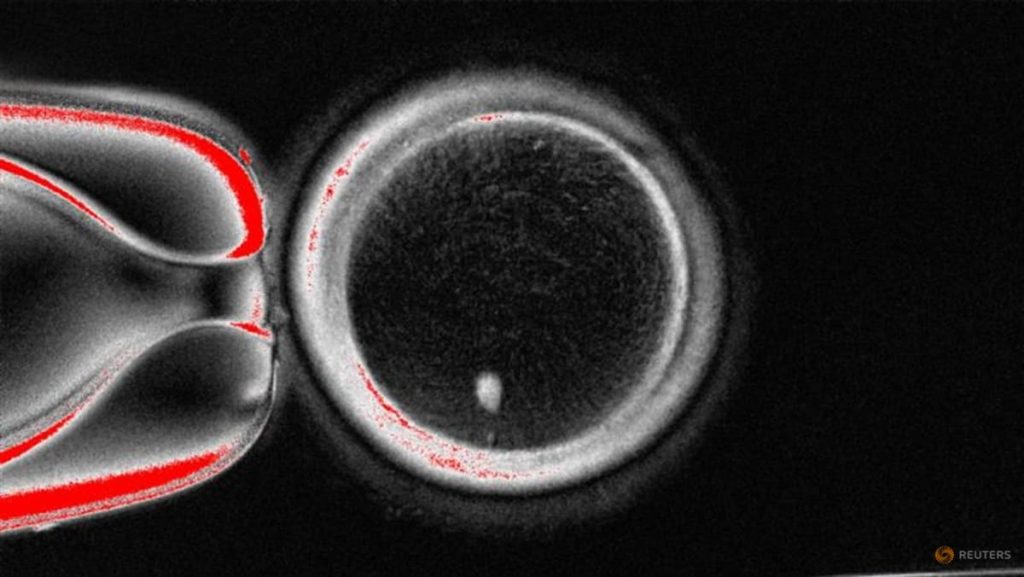

The process, which would carry significant safety concerns, involves removing the nucleus from a woman’s skin cell and inserting it into an egg, or oocyte, from which the nucleus has been removed, scientists detailed in Nature Communications.

Researchers from Oregon Health & Science University say that they solved the problem of the extra set of chromosomes by inducing a process they call mitomeiosis, which mimics natural cell division and causes one set of chromosomes to be discarded, leaving a functional egg, according to the report.